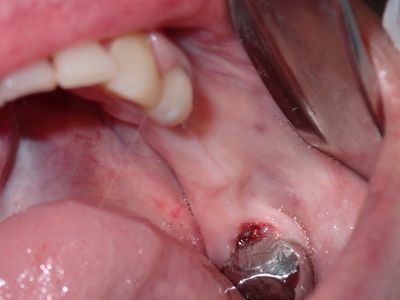

JGolos - lrq implants

relatively straight forward implant placement.